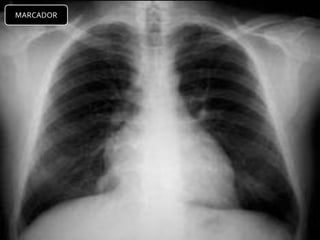

TELERADIOGRAFIA DE TX.

MARCADOR

CRITERIOS DE EVALUACION RX.

TX.

 Pulmones desde ápex

hasta senos costo

diafragmáticos

   Pulmones y corazón sin

rotación.

   10 pares de costillas.

   Sombra área de la

tráquea centrada sobre

la columna.

   Balance en los

contrastes de la imagen

(exposición adecuada).

INTERPRETACION

 Revisar estructuras

óseas.

   Partes blandas.

   Espacios intercostales.

   Parénquima pulmonar

   Nivel de los senos

costodiafragmaticos.

   Neumatización.

   Trama alveolo-pulmonar

   Silueta cardiaca

   Cayado aórtico.

CRITERIOS DE EVALUACIONRX. TX.  Pulmones desde ápex hasta senos costo diafragmáticos  Pulmones y corazón sin rotación.  10 pares de costillas.  Sombra área de la tráquea centrada sobre la columna.  Balance en los contrastes de la imagen (exposición adecuada).

INTERPRETACION  Revisar estructuras óseas.  Partes blandas.  Espacios intercostales.  Parénquima pulmonar  Nivel de los senos costodiafragmaticos.  Neumatización.  Trama alveolo-pulmonar  Silueta cardiaca  Cayado aórtico.